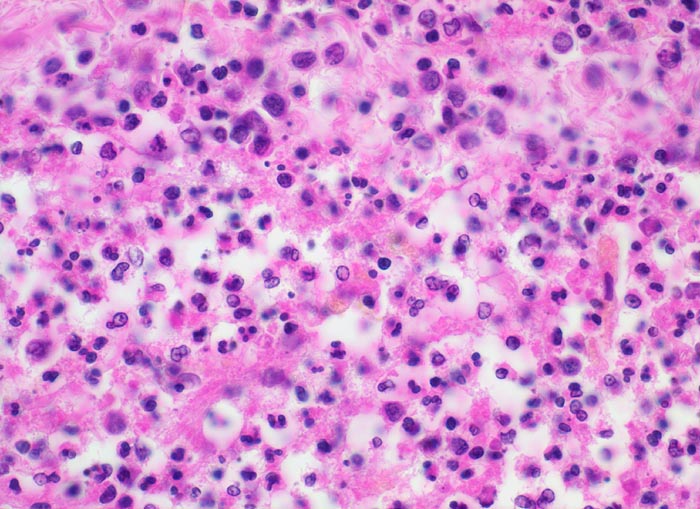

PathoPic – image database / PathoPic ID 5191 - Eitrige Leptomeningitis

Eitrige Leptomeningitis

Ausschnitt aus dem eitergefüllten Subarachnoidalraum: Wenig Fibrin, segmentkernige und stabkernige neutrophile Granulozyten, Kerntrümmer von zerfallenen neutrophilen Granulozyten.

Bronchopneumonie. Nachweis von Pneumokokken im Abstrich von der Hirnoberfläche und von der Lunge.